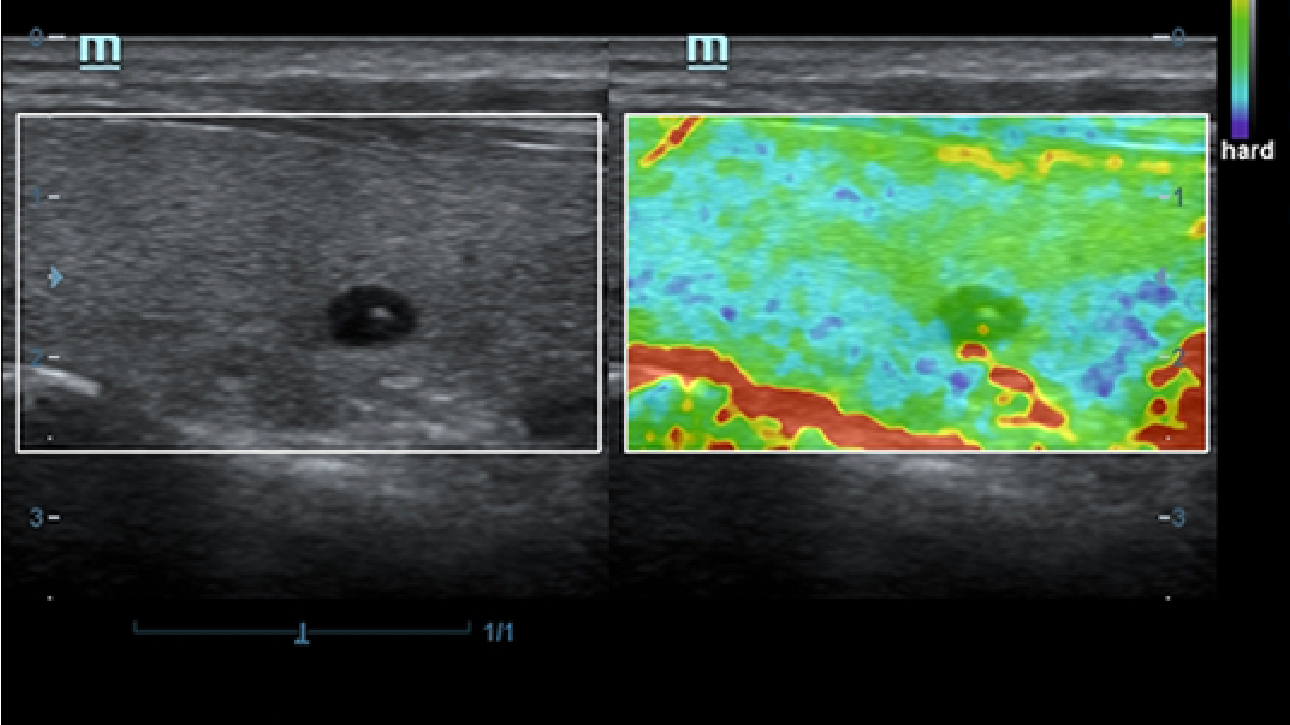

Klinische Bilder